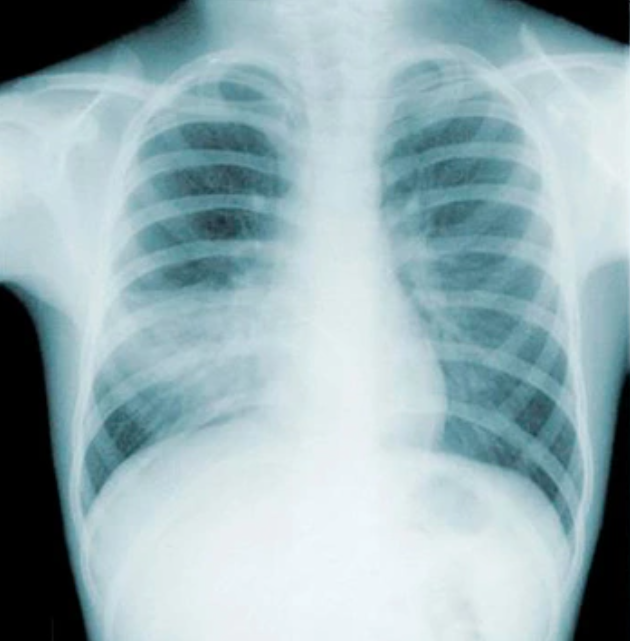

• Рентгенография органов грудной клетки (очаг инфильтрации + клиника)

КТ (при неясной картине, подозрении на осложнения)